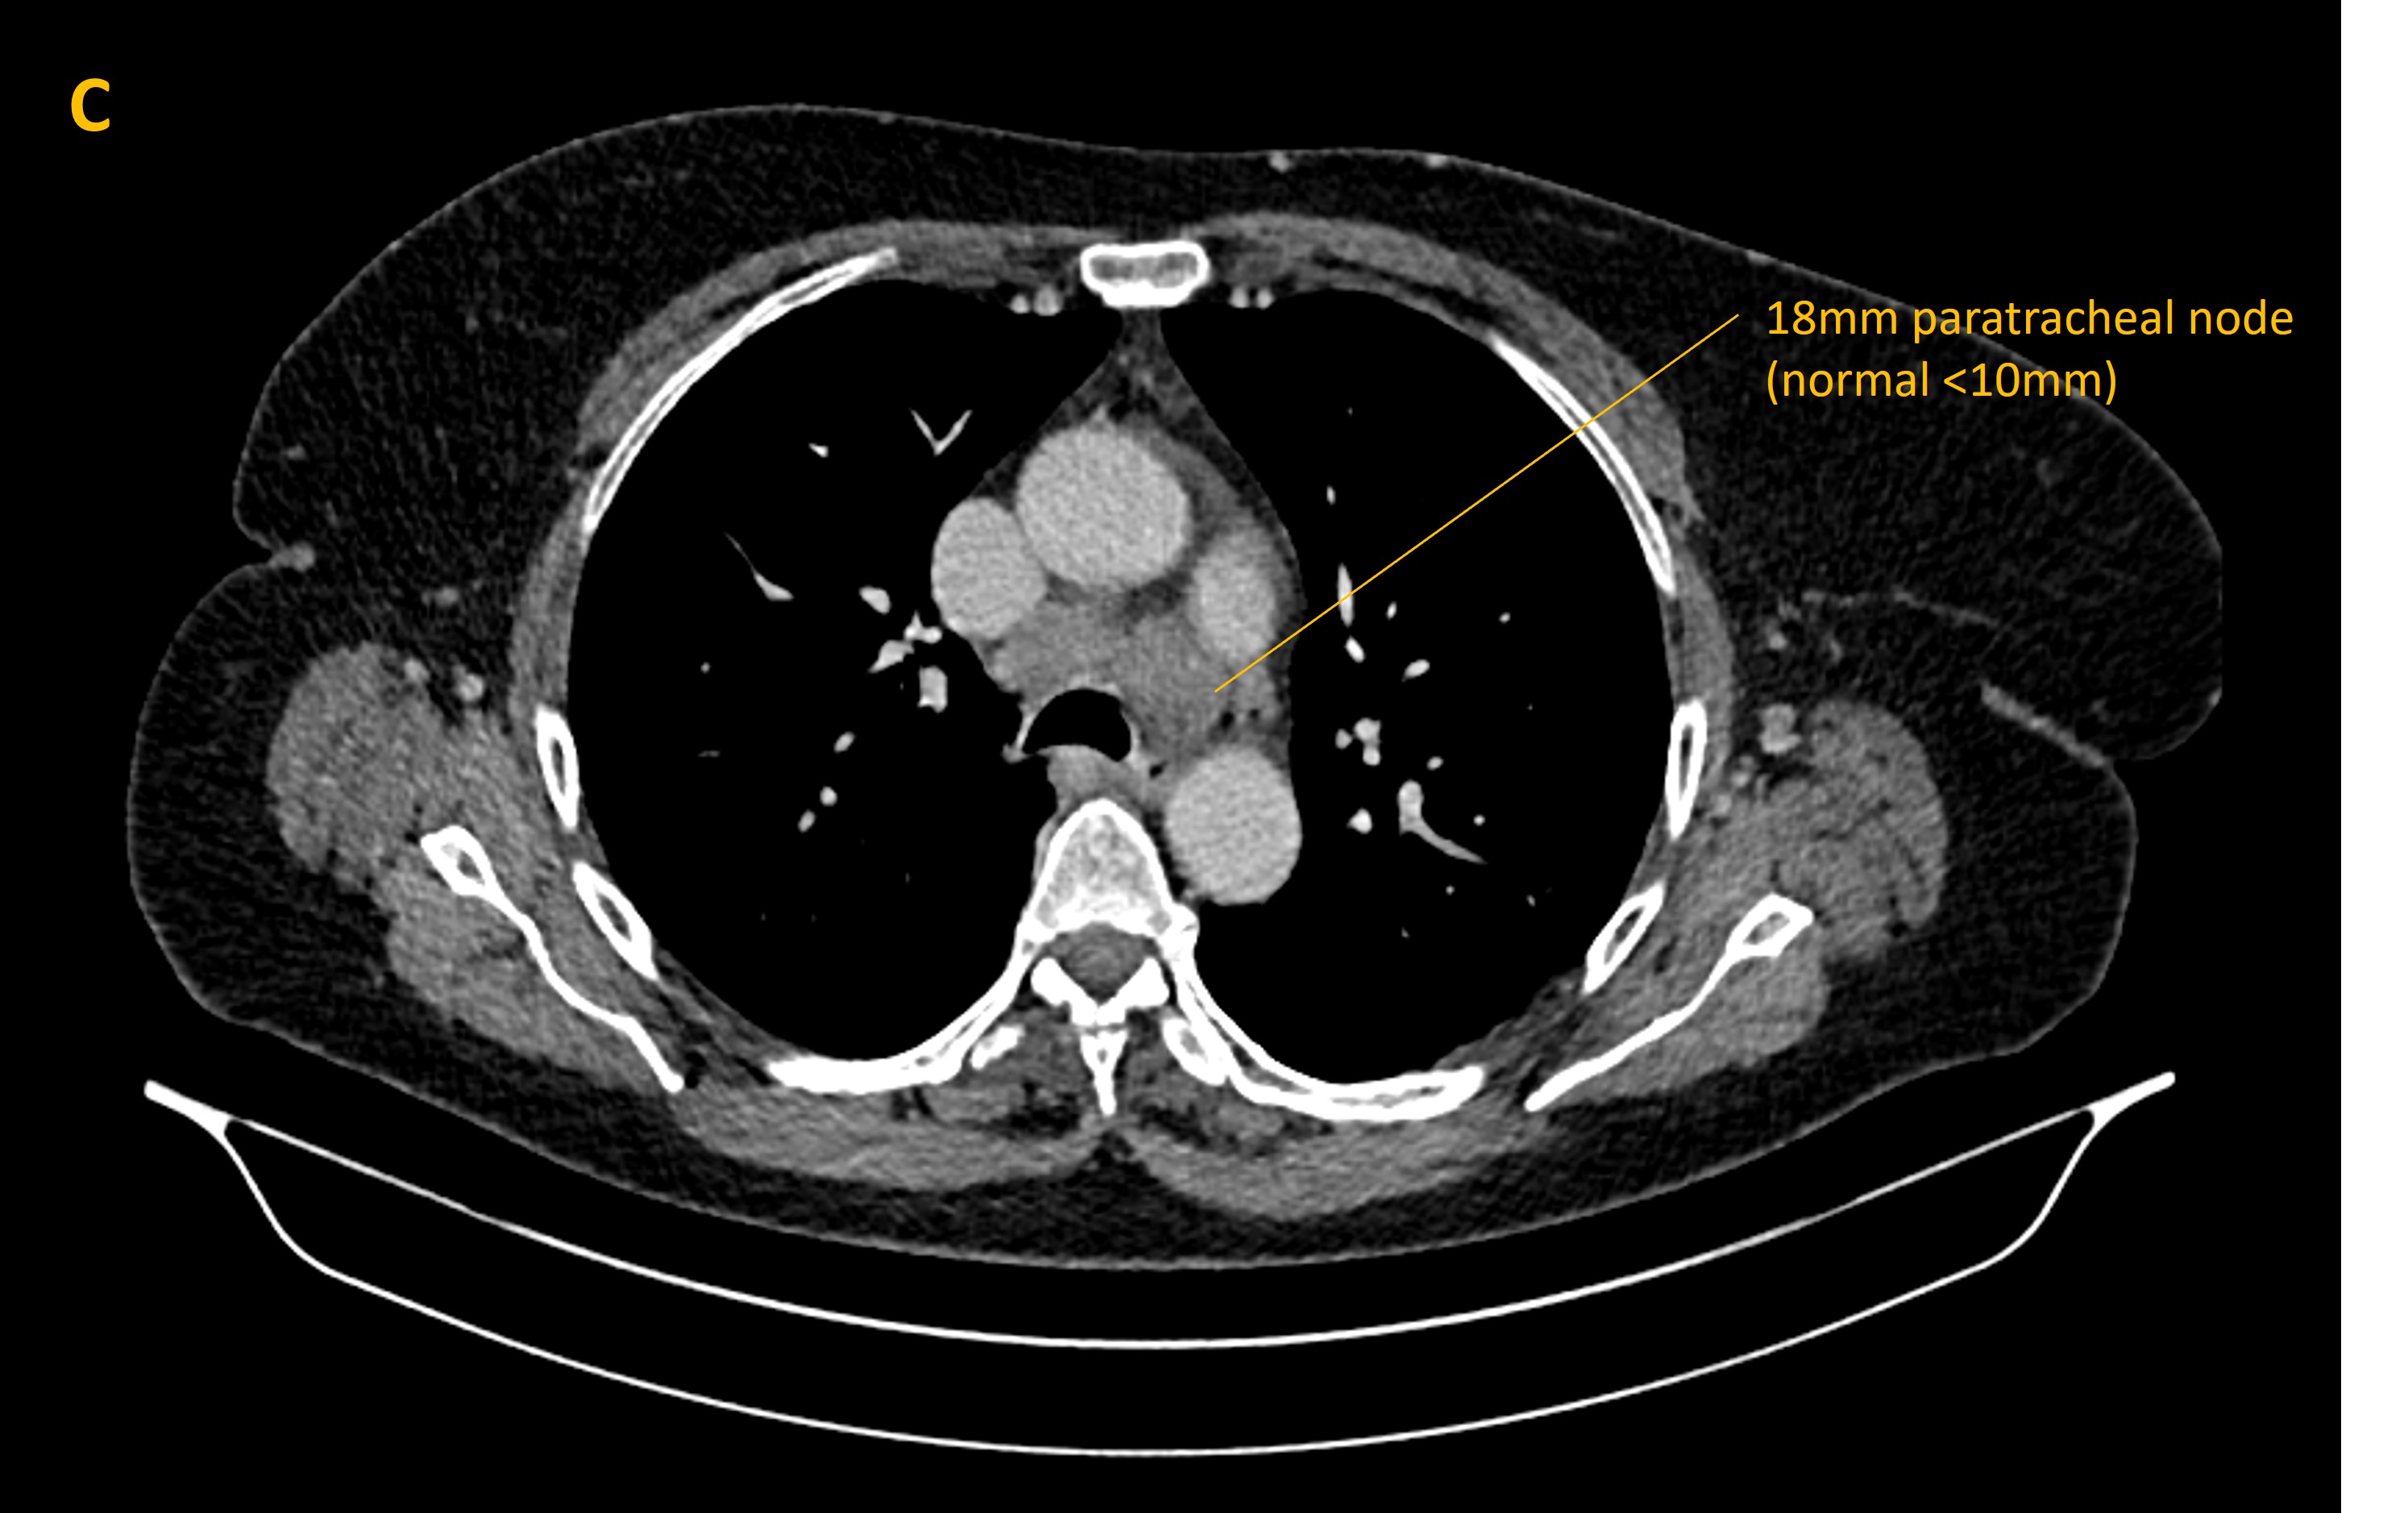

A CT of the body showed enlarged lymph nodes in the mediastinum, and a biopsy sadly showed small cell lung cancer (SCLC) invading the nodes. Paraneoplastic antibody tests found the anti-Hu antibody, which is recognised in SCLC-associated limbic encephalitis.